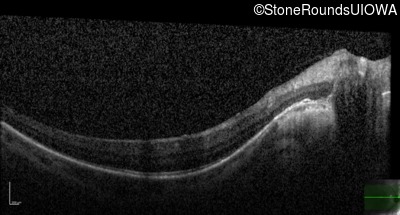

AD Retinitis Pigmentosa (IA1aii)

Age at visit:

53 years

OD

OS

20/16 -2

20/16 -1

OCT Stack

Diagnosis & molecular findings

Disease

Gene

Allele 1 variant(s)

Allele 2 variant(s)

Inheritance mode

AD Retinitis Pigmentosa

SNRNP200

Ser1087Leu TCG>TTG

AD